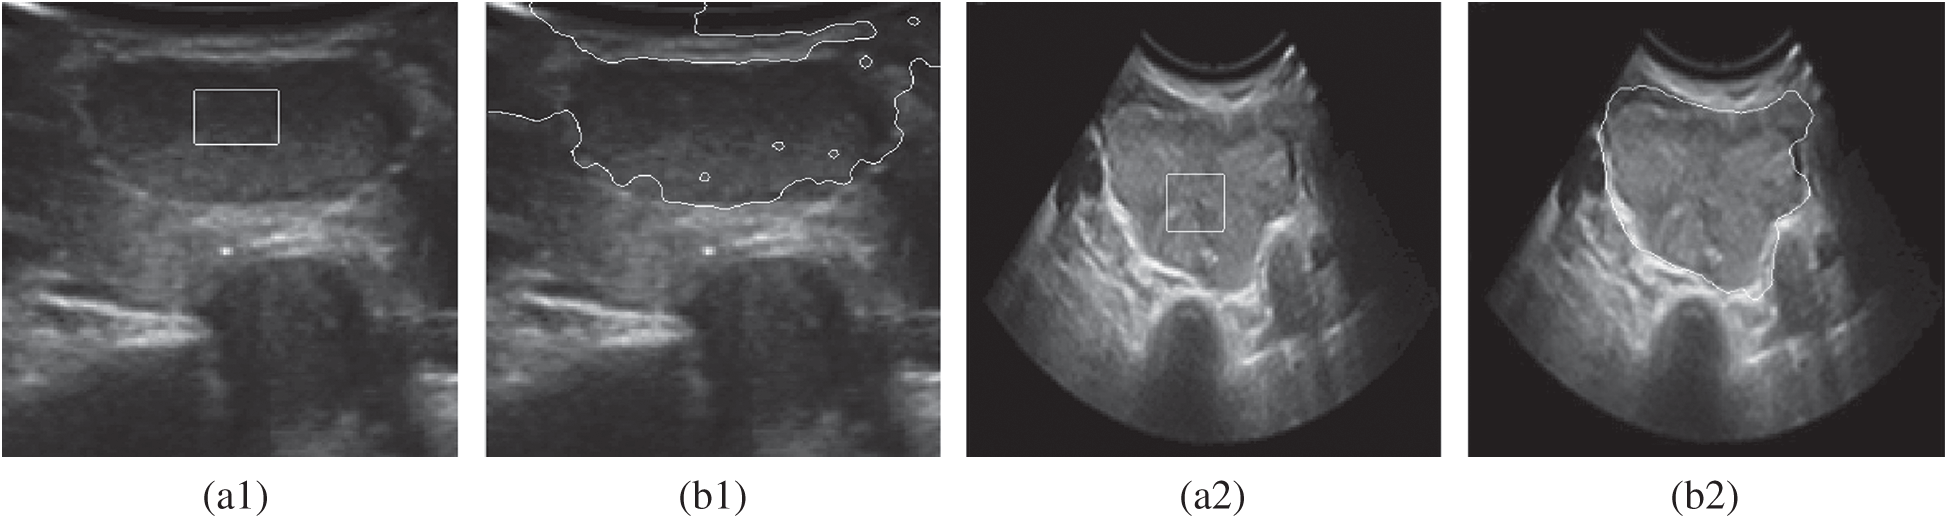

DRLSE model features simple numerical solution and speedy convergence. Moreover, it does not need to reinitialize the level set. However, for the segmentation of medical ultrasound images, due to the low contrast between tissues and organs in ultrasound images, fuzzy boundary, intensity inhomogeneity in images before and after ultrasonic field, the

Figure 1: A comparison of the inaccurate boundary locations of the DRLSE model. (a1) Original image1 (b1) DRLSE segmentation (a2) Original image2 (b2) DRLSE segmentation

The problem is that when an edge-stopping function deals with weak edges, it is not zero at the weak edge due to the relevant small gradient of the weak edge [19]. Therefore, it is necessary to search for a new edge-stopping function which can guarantee the convergence at the weak boundary.